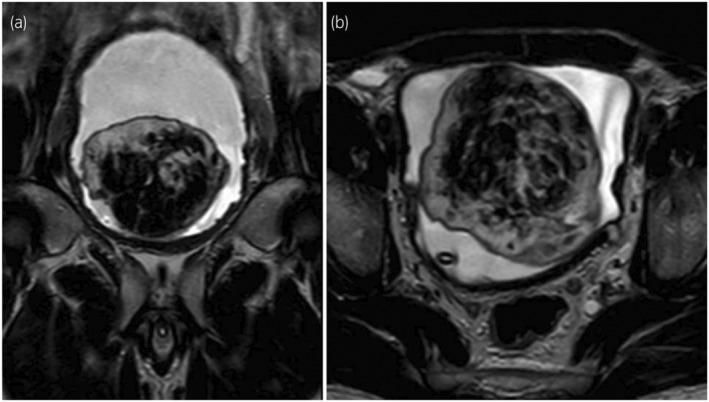

A 44-year-old male patient with obstructive uropathy was referred to our unit for workup. Ultrasonography and MRI of the pelvis showed a large, well-circumscribed bladder mass, also visualized cystoscopically. This mass was excised en bloc using the Pfannenstiel approach. Histopathological and immunohistochemical analyses revealed a solitary fibrous tumor.

一名患有梗阻性尿路病的44岁男性患者被转诊至我科进行检查。骨盆的超声和磁共振成像显示一个大的、边界清晰的膀胱肿块,膀胱镜检查也可见到。采用Pfannenstiel入路将该肿块整块切除。组织病理学和免疫组织化学分析显示为孤立性纤维瘤。